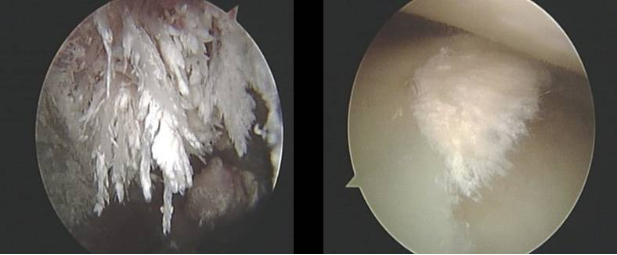

從鏡頭中可以看到,患者的關(guān)節(jié)囊里面有許多像石灰一樣的小石頭,各個地方都有。因為患者沒有做雙能CT掃描,我們不知道里面到底有多少痛風(fēng)石,只能不斷地探索關(guān)節(jié)囊里面各個地方,不斷地清理和沖洗。做針刀鏡的時候,會有源源不斷的水跟著鏡子進(jìn)入關(guān)節(jié)囊里,然后有一個負(fù)壓吸引管將水吸引出來。通過透明的管,我們看到許許多多白色的類似石灰石一樣尿酸鹽從關(guān)節(jié)流向負(fù)壓吸引瓶。

如上圖,箭頭所指的粘在袋子底部的白色類似石灰一樣的物體,就是從關(guān)節(jié)里面沖洗出來的痛風(fēng)石。出院的時候,G先生說:“經(jīng)過治療、沖洗以后,我感覺膝蓋比以前輕松了很多。”